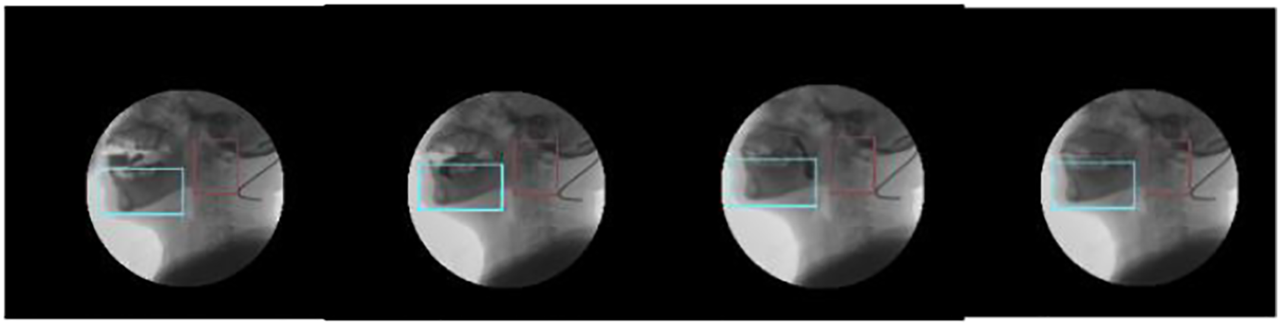

In this paper, we propose an improved inter-frame differential method (Figure 6), which uses a combination of watershed segmentation, discrete point tracking, and dynamic tracking frame (rectangular region containing the target region) to improve the shortcomings of the differential method.

Using this method (Figure 7) for inter-frame differencing, the effect of residual images can be well eliminated, and combined with watershed segmentation, the contours and regions of the moving target can be obtained more accurately.

Compared with processing the whole image, bilateral filtering of the target region can effectively reduce the impact of noise on image processing. Gray scale stretching makes the span of regions with similar gray scale increase, which is easy to determine and segment. Then the pre-processed image is subjected to improved inter-frame differencing, and the target region obtained is subjected to the open and close operation in morphology to remove the voids and line regions, and the location of the target is determined by combining the discrete point location and grayscale information (Figure 8).